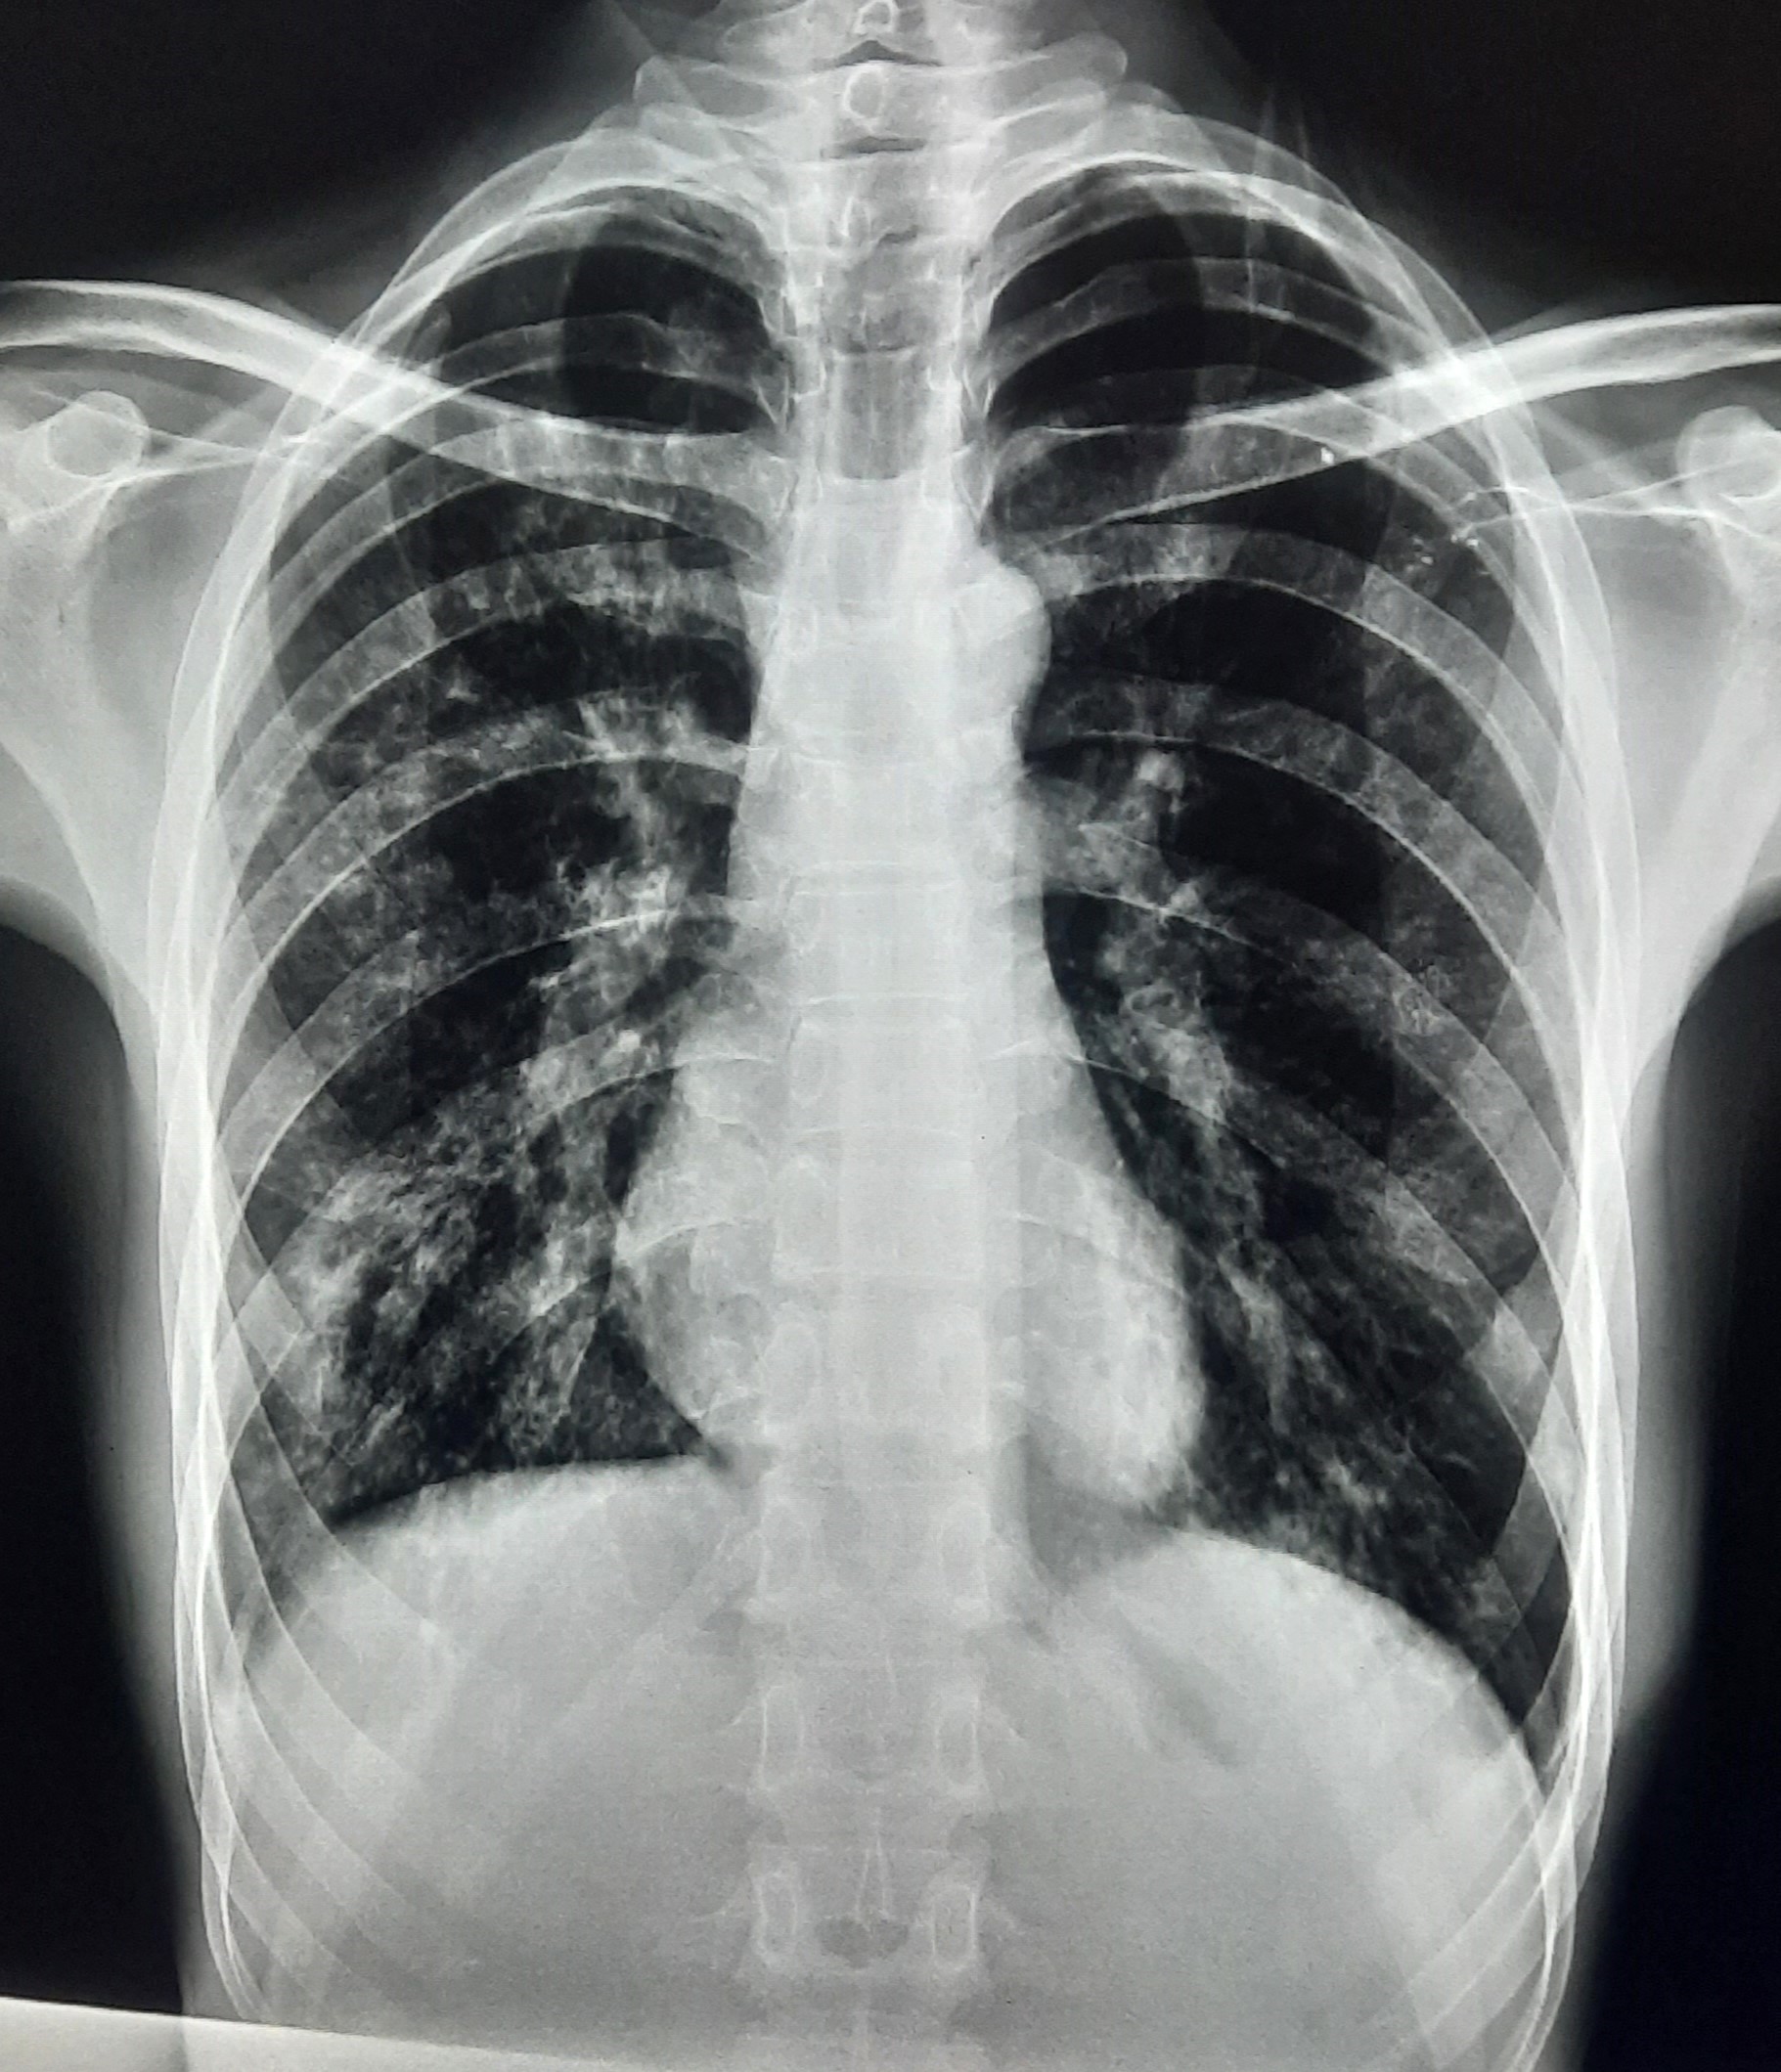

| 132 | IGGMC, Nagpur, Nagpur | P2 | 29-4340 | Ritesh Chaudhary | Consent taken on Paper | 30 Yrs. |

Provisional Diag : Post TB Sequelae

Final Diag : Post TB sequalae With Fibro Cavitary Changes |

Post TB Sequelae | Bilateral Upper Zone Fibro Cavitary Changes With Right Upper Zone Fungal Ball With Bilateral Haziness With Tenting Of Diaphragm | Abnormality visible on x-ray |